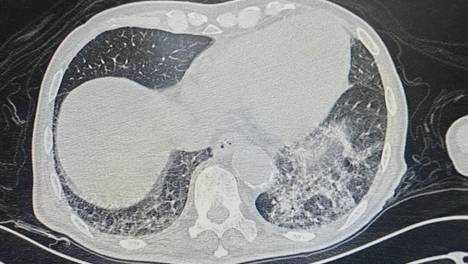

精准穿刺破困局!北京老年医院呼吸内科成功完成肺部微小结节诊断术

近日,北京老年医院呼吸内科刘前桂主任医师带领呼吸内科团队,在放射科密切配合下,成功为一名68岁的肺部微小结节患者实施CT引导下肺结节穿刺术。科室还邀请国内著名专家定期来医院查房,诊治疑难病例,指导危重症患者的…